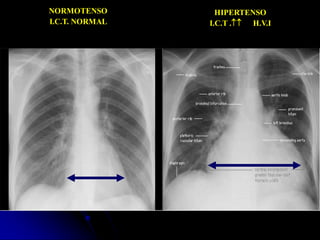

NORMOTENSO

I.C.T. NORMAL

HIPERTENSO

I.C.T . H.V.I